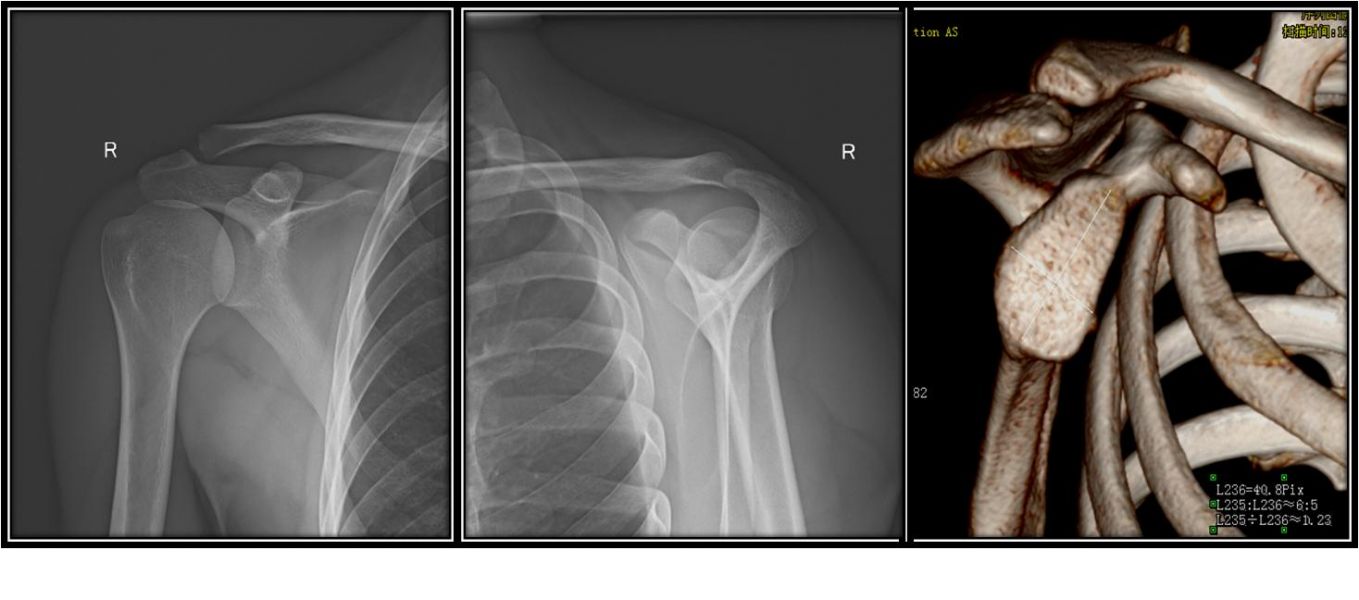

术前影像资料

经患者同意后,赵峻主任医师带领团队于2019年1月10日为患者成功实施右肩关节镜检、关节清理、Bankart损伤修复术。手术十分顺利,皮肤上仅有4个约0.5cm小切口。术后给予指导康复训练,患者很快就康复出院。术后一年,患者回骨一科复诊,功能恢复良好,无复发脱位,几乎看不到疤痕。

术后仅有4处约0.5cm小切口图及术后影像资料